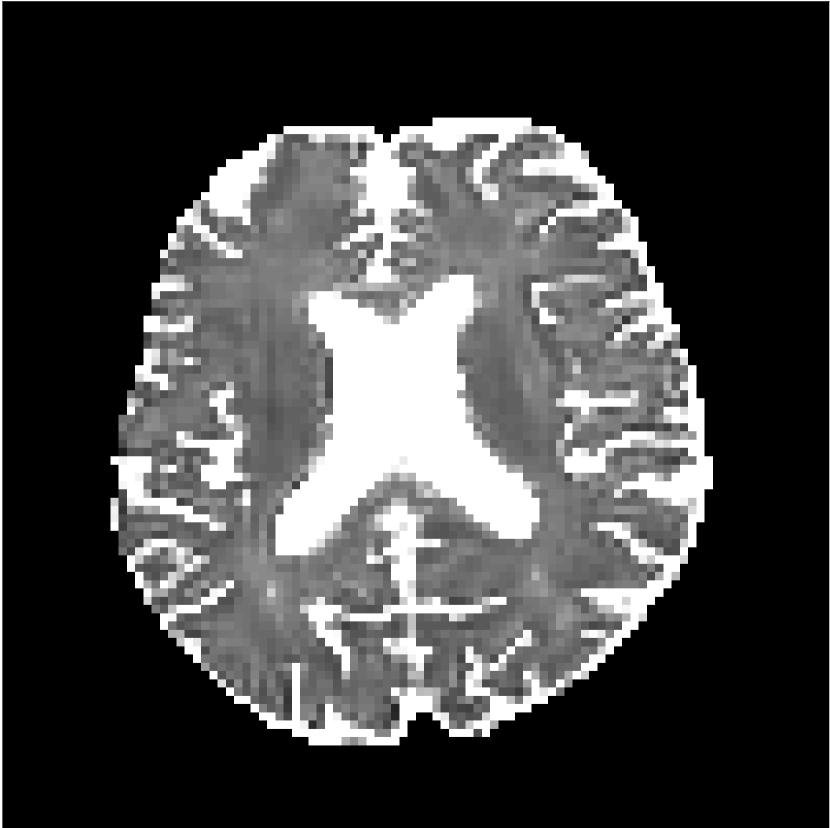

Figure 9 shows parameter maps for the different methods without partial Fourier (No PF) and with 5/8ths partial Fourier (5/8 PF). Mean diffusivities calculated from the raw DWI data (Raw) show notable noise and Gibbs ringing artifacts, while this is substantially removed with the state-of-the-art (SoA) method. However, the state-of-the-art method begins to lose its ability to compensate for the Gibbs ringing and resolution loss when partial Fourier is utilized in the acquisition. The effects of partial Fourier increases are primarily evident in the enlargement of the lateral ventricles and the presence of black lines in the vicinity of the lateral ventricles. The MCNN model is able to compensate somewhat for the ringing effects, but begins to introduce substantial artifacts at the 5/8ths partial Fourier factor, whereas the CCNN model continues to give high-quality mean parameter maps across all PF factors.

Raw

SoA

MCNN

Standard PF

CCNN

s/mm2

No PF

MD, m2/ms

5/8 PF

FA

MK

Similar trends are observed in the other diffusion parameter maps.